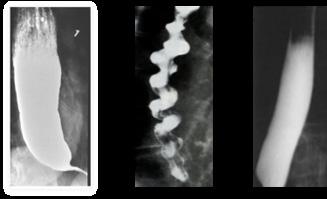

♦ Radiografía baritada: imagen en pico de pájaro o punta de lápiz

Espasmo difuso del esófago

♦ Producido por contracciones terciarias

♦ Dolor torácico con alimentos fríos o calientes

♦ Radiografía baritada: imagen en sacacorcho

Esclerodermia

♦ Producido por fibrosis y/o atrofia del esófago con un EEI hipotónico (reflujo)

♦ Pirosis + fenómeno de Raynaud

♦ Radiografía baritada: imagen en tubo rígido

Figura 12. Una delgada membrana semilunar se proyecta hacia la luz en la parte superior del esófago, junto con la anemia por deficiencia de hierro (coiloniquia) y la disfagia forman parte de la tríada clásica del síndrome de Plummer-Vinson. Figura 13. Trastornos motores del esófago. A: Acalasia; B: Espasmo difuso del esófago; C: Esclerodermia Figura 14 Cáncer de esófago produce disfagia mecánica progresiva con baja de peso significativo